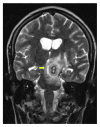

We report a case of a Somali refugee who presented in the second trimester of her first pregnancy with a four-week history of gradual right-sided sensomotoric hemisyndrome including facial palsy and left-sided paresis of the oculomotorius nerve causing drooping of the left eyelid and double vision. Cranial magnetic resonance imaging revealed a solitary brainstem lesion. Upon detection of hilar lymphadenopathy on chest X-ray (CXR), the diagnosis of disseminated tuberculosis with involvement of the central nervous system was confirmed by PCR and treatment induced with rifampicin, isoniazid, pyrazinamide, and ethambutol. The patient had a steady neurological improvement and a favorable pregnancy outcome.